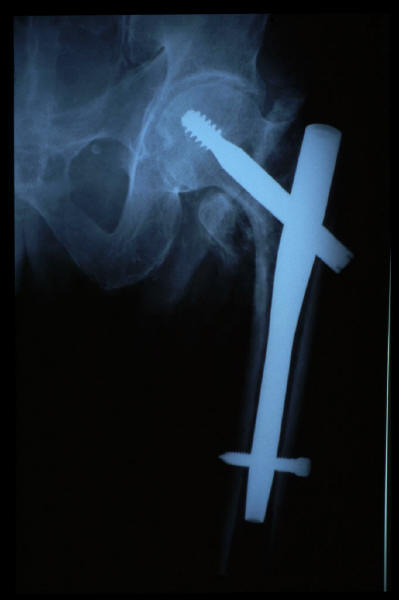

Fractura intertrocantérea de fémur, osteosíntesis

osteosíntesis fractura fémur